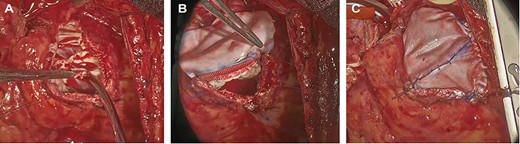

Intraoperative photograph; (A) The remnants of the pulmonary valve; (B, C). pulmonary valve replacement and patching.

The surgery was performed through median re-sternotomy, and cardiopulmonary bypass was established with arterial cannulation into the right femoral artery and venous cannulation into the right femoral vein and later into the superior vena cava. Cardiac arrest was induced with retrograde cold blood cardioplegia. A Dacron patch was seen from the right ventricular outflow tract to the main trunk of the pulmonary artery, and when an incision was made, a severely destroyed pulmonary valve was observed. Remnants of the pulmonary valve and the myocardium of the right ventricular outflow tract, which was stenotic, were removed (Fig. 2a), and pulmonary valve replacement and patching were performed using a bioprosthetic valve (Epic mitral 29 mm, St. Jude Medical, Inc., St Paul, MN) and bovine pericardium (Fig. 2b and c). The aortic valve was observed through an aortic incision. It was tricuspid, and the right coronary cusp was prolapsed. There was no vegetation suspicious for infective endocarditis. A mechanical valve (Regent 27 mm, St. Jude Medical, Inc., St Paul, MN) was used for aortic valve replacement. The minimum rectal temperature was 31.4°C, extracorporeal circulation time was 355 min, and aortic cross-clamp time was 184 min.